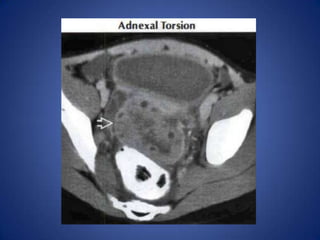

• Gynecologic Causes

– Adnexal Torsion

Gynecologic Causes

• Many, including adnexal infection & masses,

torsed ovary, endometriosis, etc.

• Look for evidence of mass &/or inflammation

Gynecologic Causes • Many,including adnexal infection & masses, torsed ovary, endometriosis, etc. • Look for evidence of mass &/or inflammation centered on adnexa, rather than bowel • Uterine Fibroids – May torse , undergo degeneration or infarction, lead to acute pain – Heterogeneous soft tissue masses within enlarged uterus, ± focal calcifications within masses